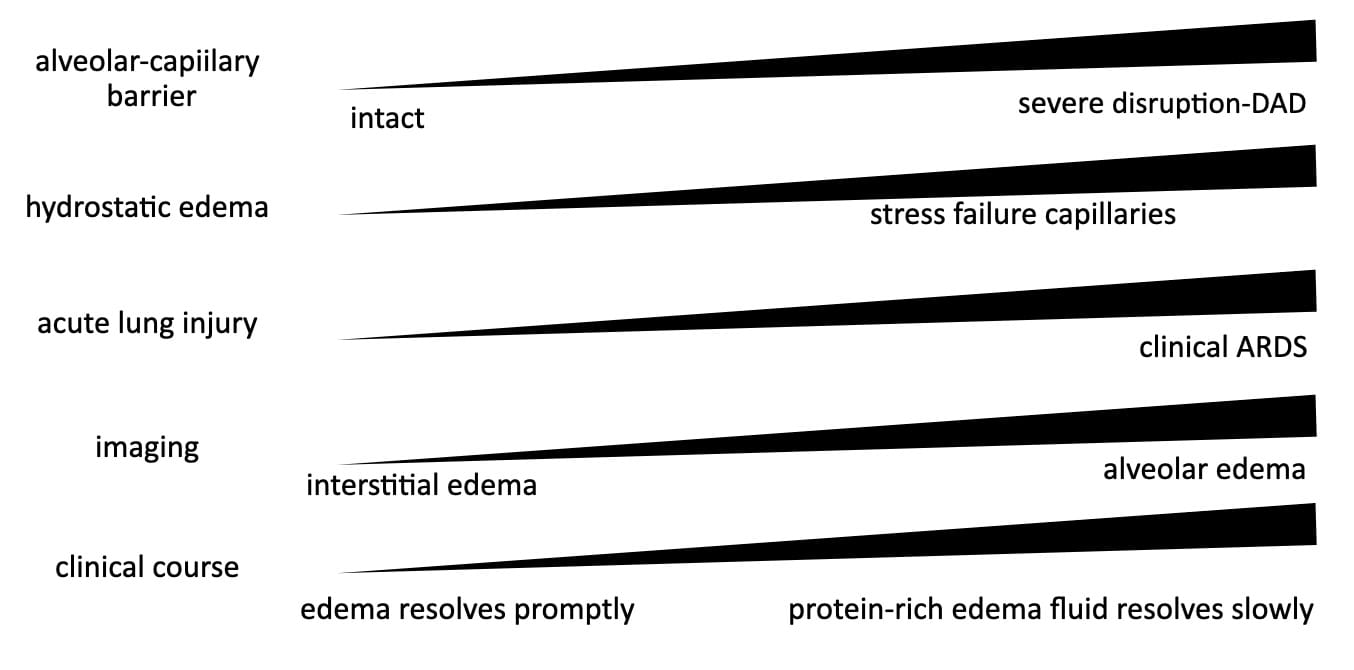

A continuum of acute lung injury, depicted in this modified graphic from an article by Ketai and Godwin.